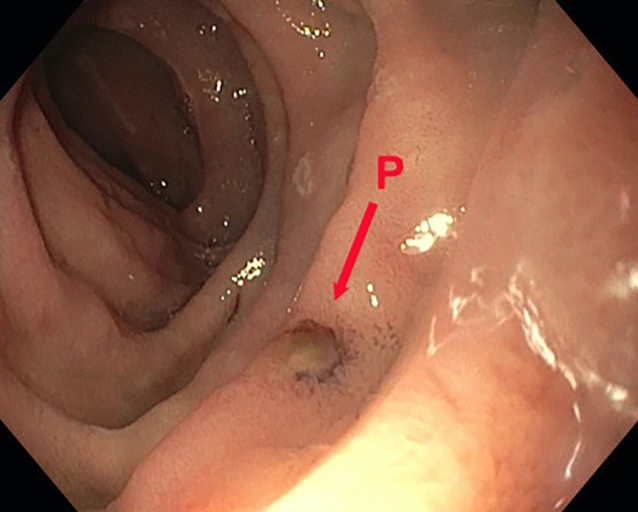

Die dOFD hat einen Durchmesser von nur 6 mm. Die transnasale Einführung erfolgte unter endoskopischer Sicht in gleicher Technik wie bei einer gastroduodenalen Ableitsonde. Der intestinale Ernährungsschenkel der dOFD wurde endoskopisch entlang des Pylorus in das Duodenum vorgeschoben und die dOFD mit dem offenporigen Folienabschnitt durch weiteres Vorschieben tief im Duodenum, die Defektregion überdeckend, platziert (Abb. 3).

Abb. 3

Platzierungsmanöver der dOFD. Ernährungssonde (iT), Übergang zum folienummantelten Abschnitt (DE), übernähter Perforationsdefekt (P) des Nephrostomiekatheters mit perifokalem Ödem und lokalen Entzündungszeichen